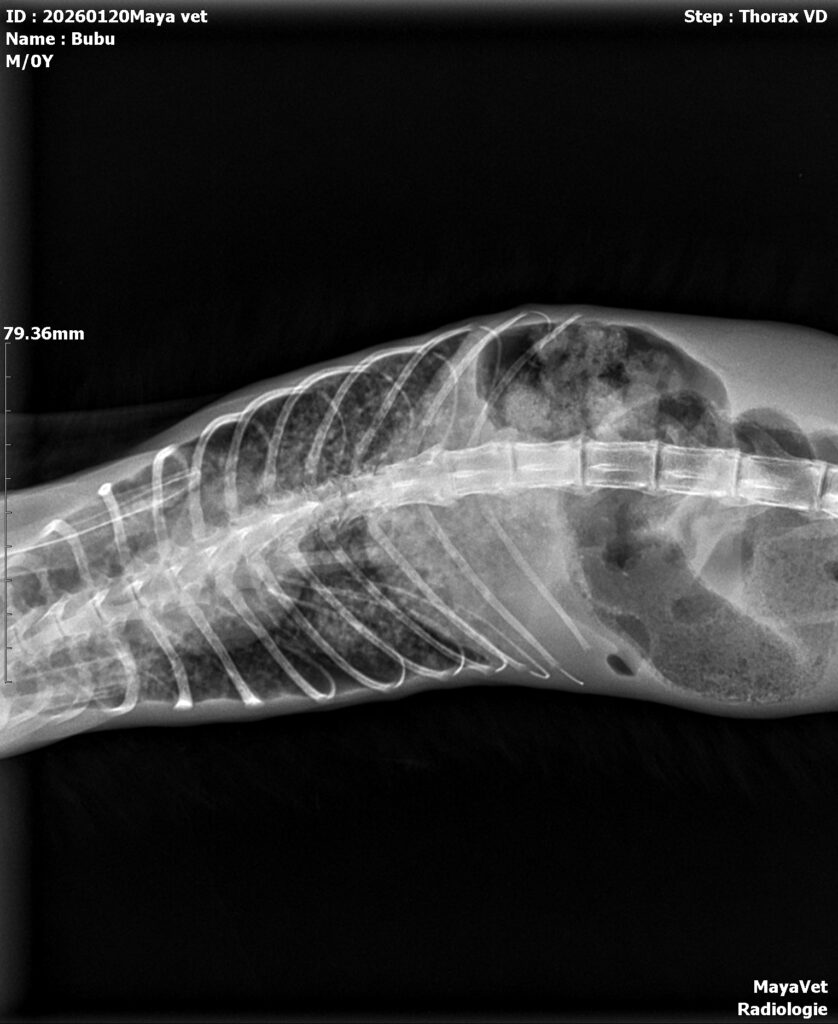

Ce ne îngrijorează: Respirația este încă îngreunată. Radiografia toracică ne-a confirmat ceea ce ne temeam: Bubu se luptă cu probleme pulmonare severe. Va avea nevoie de tratament prelungit și de urmărire atentă din partea medicilor.

Radiografia toracică a fost oferita gratuit. La tot ce a fost posibil s-a aplicat o reducere de 50%.